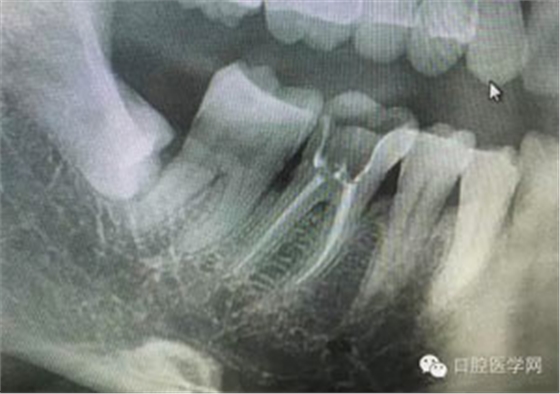

病例1:患者迫切希望保留自己的這一顆牙齒,根尖周陰影比較大,二度松動(dòng).而且旁邊有種植修復(fù)體,和患者溝通好后,治療好后觀察一個(gè)月后冠修復(fù),因?yàn)橛蟹N植的后期修復(fù),所以有了機(jī)會(huì)觀察,術(shù)后三個(gè)月和術(shù)后四個(gè)月,根尖恢復(fù)的還算不錯(cuò),希望能夠繼續(xù)觀察下去.這樣子的病例,做的時(shí)候我們一定要非常的小心,和患者要有充分的溝通以及不同科室的溝通然后決定怎么樣做比較好,假如就是出現(xiàn)了問題,到時(shí)候我們也比較好處理些,免得我們自己到時(shí)候不好收?qǐng)觥?/span> 病例2:364647中齲的樹脂充填,現(xiàn)在樹脂的充填材料非常之多,有些時(shí)候,我們感覺有了好的材料我們就可以做出好的修復(fù),可是這是在我們有扎實(shí)的基本功的基礎(chǔ)上的,我們可以沒有那么好的樹脂,那么多的顏色選擇,修復(fù)的那么的逼真,但是我們至少要恢復(fù)患者牙齒的功能,將腐質(zhì)去除干凈,薄壁弱尖消除掉,選擇好適應(yīng)癥,給患者以盡可能好的修復(fù)。 來源于KQ88